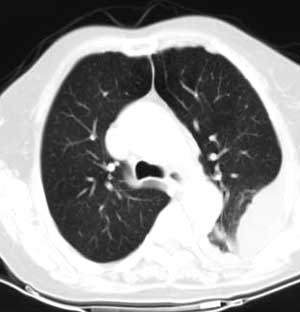

测ct值3-6hu,

既然ct值是3-6hu,还不如考虑包裹性积液。

请上传纵隔窗。目前还是支技包裹性积液(明显梭形),即使是间皮瘤并积液也少梭形的。

从图片看,包裹性积液好象更合理,梭形,ct值3-5hu(在哪看到的?);胸膜间皮瘤如此规则,不多见。

左侧背部胸膜肥厚,伴包裹性积液,不考虑间皮瘤.

同意以上各位的高见,首先考虑包裹性积液,1.胸膜间皮瘤积液量一般较大,以游离性积液更为常见,2.可以看到增厚的胸膜结节